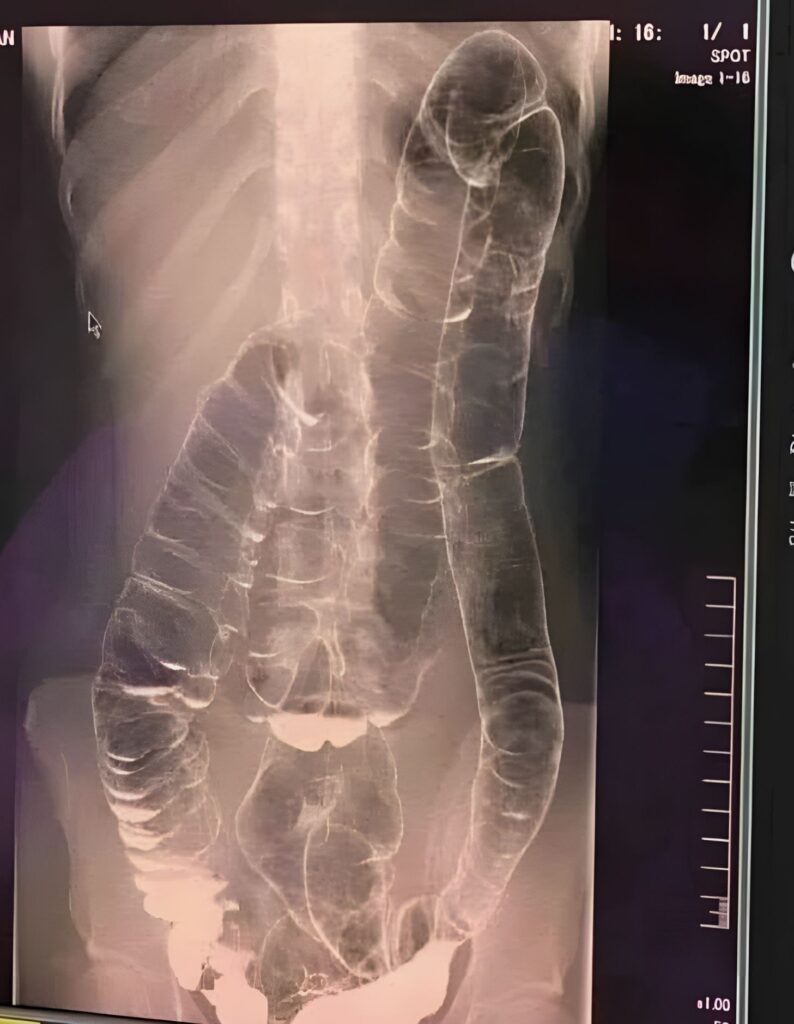

In some rare cases, chronic constipation can evolve into a medical emergency. A condition known as toxic megacolon occurs when the colon becomes severely distended due to a prolonged buildup of stool and gas. The colon loses its natural ability to contract and move waste through the intestines, leading to bloating, intense discomfort, and in severe cases, systemic infection or tissue damage.

While toxic megacolon is more commonly associated with inflammatory bowel diseases like ulcerative colitis or Crohn’s disease, extreme cases of untreated constipation can also trigger similar symptoms.

When stool accumulates, the colon stretches beyond its normal limits. Over time, this can weaken the muscular wall of the intestines and impair their ability to contract. The result is a cycle of worsening constipation and increased discomfort.